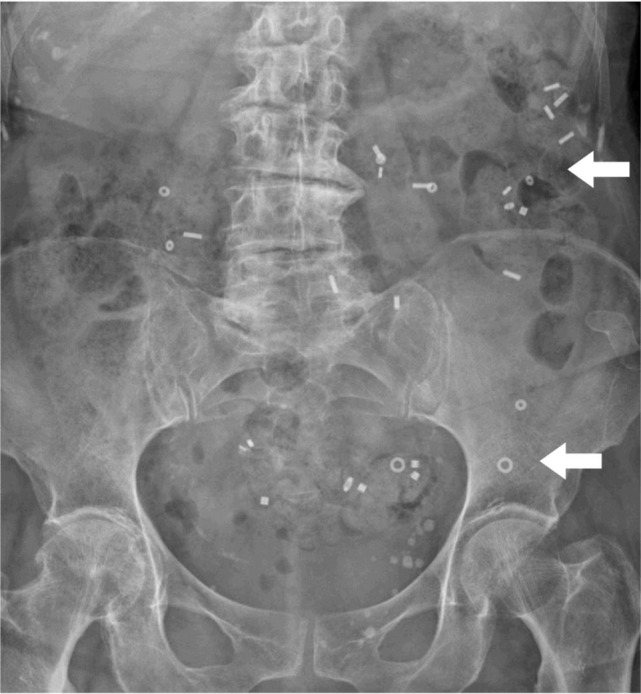

Materials and methods: In this video an 86-year-old woman with ODS and POP, suffering from a dolichocolon with rectal intussusception, an apical prolapse after total hysterectomy 1990, and occasional stress urinary incontinence underwent interdisciplinary laparoscopic surgery. A tubular anterior rectal and sigmoid resection with suture rectopexy as in a resection rectopexy (RRP) was combined with a sacrocolpopexy (SCP) using a synthetic mesh.

Abstract Image